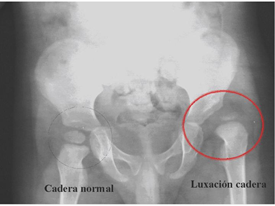

Luxación congénita de cadera(displasia del desarrollo de la cadera) Entre las malformaciones más frecuentes en ortopedia pediátrica, cabe señalar la hasta hace poco llamada luxación congénita de cadera, sustituida por el actual de displasia de cadera en desarrollo. Se ha sustituido el término congénito por desarrollo ya que en ocasiones la cadera normal al nacimiento puede presentar anormalidades más tardías. Además se acepta que al pasar el tiempo se producen cambios con lo que una cadera sub-luxable al pasar el tiempo puede estar luxada.

Ecografía o ultrasónido: Actualmente es la técnica diagnóstica de elección. Sus principales ventajas son que es una técnica no invasiva, que ha demostrado ser el método mejor y más seguro, válido para cualquier edad Su mayor utilidad diagnóstica se presenta al final del primer mes, y por ello se indica entre la 4ª y la 6ª semana en aquellos pacientes con factores de riesgo y exploración clínica dudosa. Su sensibilidad en la detección de DCC bordea 100%.